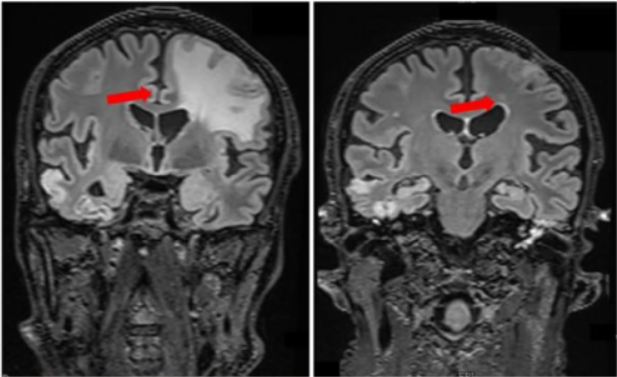

图1 | 患者1接受匹妥布替尼治疗的影像学表现:MRI在基线期(左图)及治疗3个月时(右图)的对比

患者在接受伊布替尼治疗30个月后发生疾病进展,出现癫痫

发作和右臂活动障碍。MRI显示左侧颞顶叶组织增加,累及顶叶硬脑膜,伴轻度软脑膜增强,硬脑膜增厚,大脑顶叶上部皮质新见局灶性信号改变提示实质损伤。左顶叶活检证实淋巴浆细胞

性淋巴瘤浸润(CD20+, CD79a+, Ki67 20%)。

患者进行匹妥布替尼治疗3周后右臂功能完全恢复,1个月CT显示左侧顶叶肿块缩小,3个月MRI显示硬脑膜增厚减少50%(8 vs 20mm)、病灶周围水肿

和帽状腱膜下病变完全消退。颅顶区域仍可见局灶性强化灶残留。

患者接受匹妥布替尼持续治疗7个月(仍在治疗中),血液学反应为非常好的部分缓解(VGPR),临床反应CR,影像学反应PR。